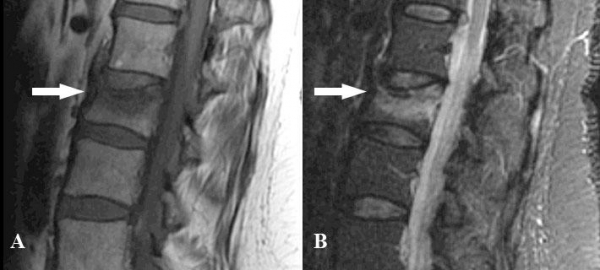

Nel sospetto di una frattura vertebrale viene eseguita una radiografia della colonna (Fig. 5). Se il sospetto clinico viene confermato si approfondisce la diagnostica ricorrendo alla Risonanza Magnetica (Fig. 6) che fornisce informazioni sul “timing” : cioè se la frattura è recente o di vecchia data.

Fig. 6 Acquisizioni RM in cui si evidenzia una frattura osteoporotica recente